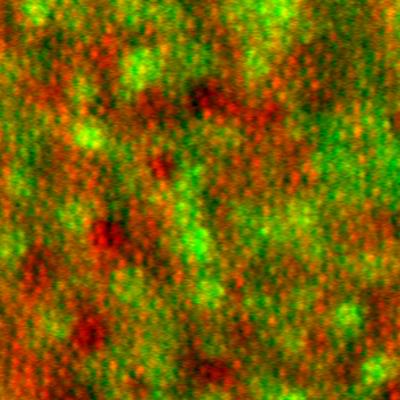

Retinal pigment epithelial cells imaged  using adaptive optics

Retinal pigment epithelial cells imaged noninvasively in a living human eye using adaptive optics. Image generated using a combination of multiply-scattered light (red) and intrinsic near-infrared autofluorescence (green).